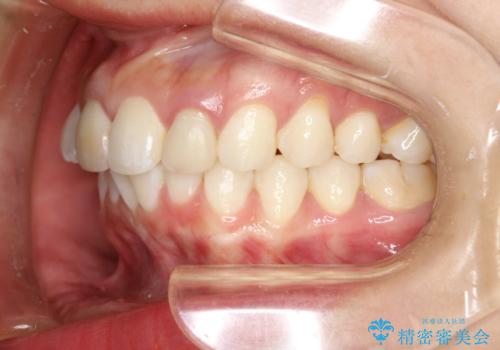

後戻りした歯並びをきれいにしたい

矯正としてはマウスピースでできましたが、患者さんの希望でワイヤー(ハーフリンガル)で矯正を行いました。

右下1が歯肉退縮していたため、アーチを拡げないように歯と歯の間を削って隙間をあけて並べています。